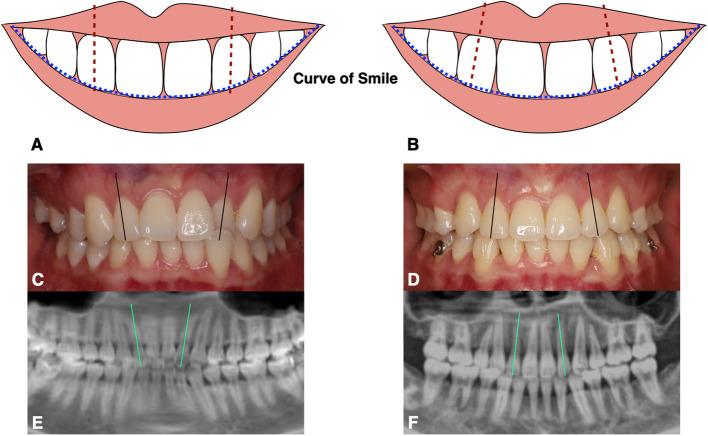

This study analyzed 27 patients (mean age 21.1 ± 4.9 years; 18 women, 9 men) who underwent extraction with clear aligners. In total, 54 maxillary lateral incisors were included-each patient contributed two teeth. CBCT scans were obtained at pretreatment and refinement. The projection of the midpalatal suture on the panoramic image helped measure the axial angulation of the maxillary lateral incisors. Three-dimensional reconstruction was performed using Mimics, and the maxillary structure superimpose method was employed to measure the horizontal distance of the maxillary lateral incisors. Influencing factors, including lateral incisor attachment, lateral incisor horizontal movement distance, upper dentition retraction method, and lateral incisor crown-to-root ratio, were analyzed. P < 0.05 was considered statistically significant.

Maxillary lateral incisors are prone to distal inclination during orthodontic extraction using a clear aligner (P < 0.001). Notably, the angulation of maxillary lateral incisors significantly decreased in both groups, with larger decreases in the nonattachment groups (P < 0.001). Significant differences were observed between different retraction methods (P < 0.05) and horizontal movement distances of the lateral incisors (P < 0.001), but none among the different crown-to-root ratios (P > 0.05).

During extraction by clear aligner, changes in the mesiodistal angulation of the maxillary lateral incisor should be considered to ensure satisfactory treatment outcomes. By adding attachments and designing the canine first retraction method, the distal inclination of the lateral incisors can be reduced.